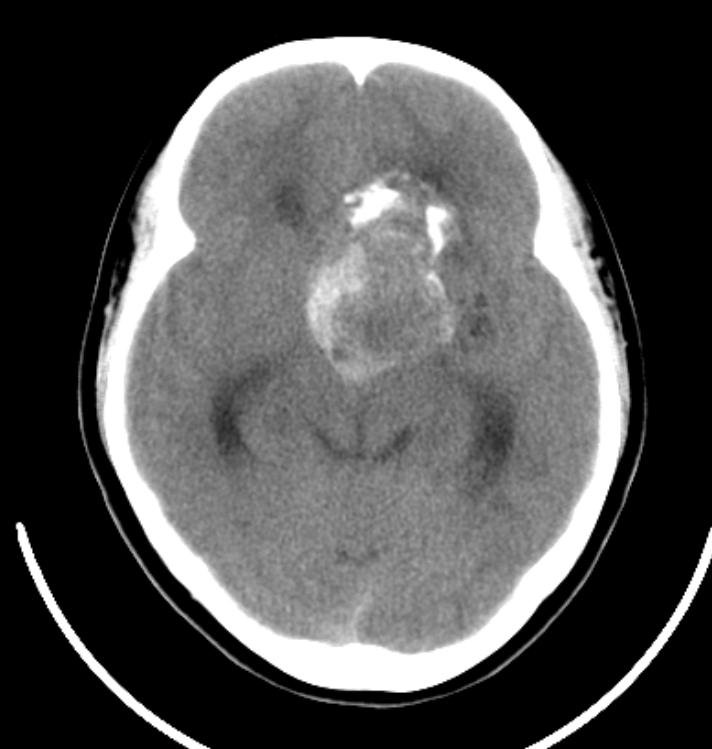

鞍上见一巨大椭圆形、分叶状高、等、低混杂密度肿块,明显占位效应,侧脑室额角、三脑室及四脑室内见高密度区,脑室系统扩大。

定位:鞍上池,肿块呈囊实性,并可见蛋壳样和斑块样钙化,患者13岁,有视力障碍。考虑颅咽管瘤!

鞍上占位,肿块为囊实性,并可见蛋壳样和斑块样钙化。第三、四脑室及侧脑室前角积血,符合颅咽管瘤伴发出血。

鞍上囊实性肿瘤,瘤较大,部分生长于第三、四脑室,并向后推压中脑。其囊壁可见“壳”样钙化,实质部分有不规则斑片状钙化及出血。与周围组织有粘连。因所提供影像不全,故蝶鞍形态不明确,但蝶骨大翼骨质有破坏。

意见:颅咽管瘤,伴出血(出血源于肿瘤脑室部分,顺脑脊液弥散)。